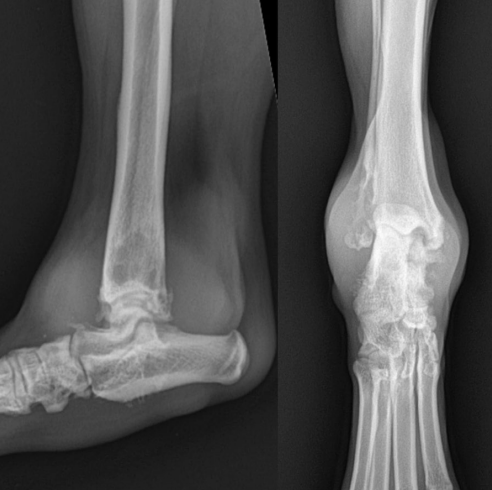

- 관절 양측에서 뼈의 변화가 나타남 - subchondral bone & cortex의 lysis, new bone production

![]() | - lining의 변화 - 오른쪽은 뼈가 다 녹아 절단할 수밖에.. |